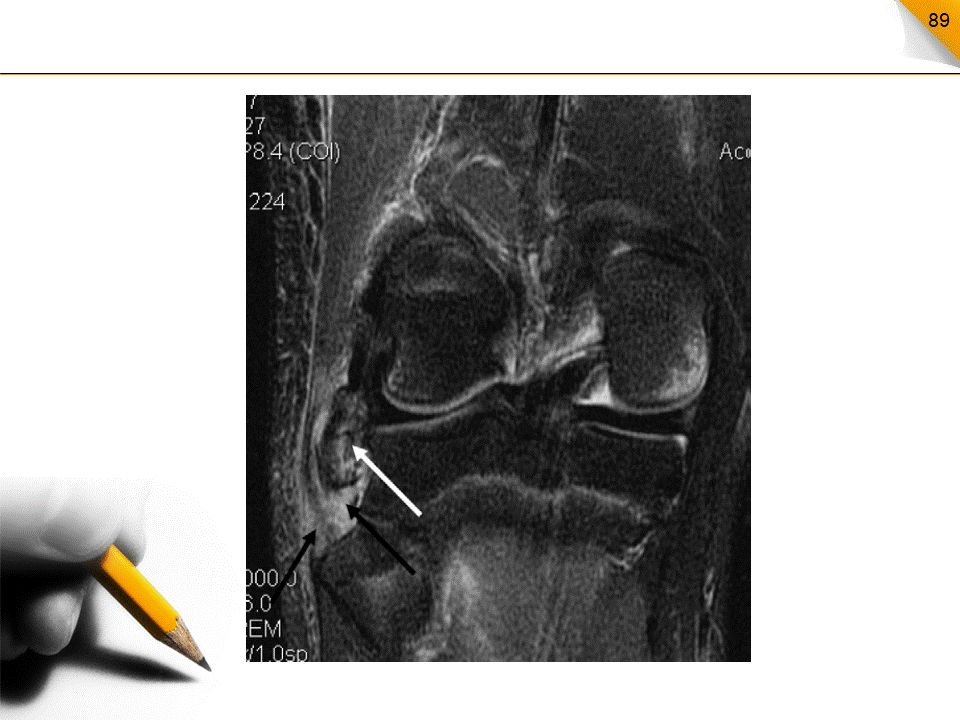

内侧副韧带撕裂

膝关节屈曲状态下,外展力的作用通常位于股骨髁的附着处,其次位于中段,发生在胫骨附着处则很少见可伴囊韧带、内侧半月板和ACL联合撕裂MRI:冠状面显像佳,韧带信号和形态改变